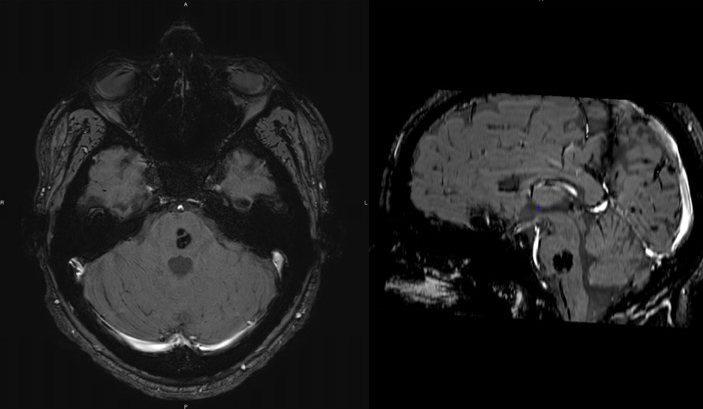

Vous demandez une IRM cérébrale injectée dont voici 2 clichés. La lésion du tronc cérébral est identifiée comme étant un angiome sans signe de saignement récent.

Source : M. Philibert.

L’IRM cérébrale retrouve une lésion du tronc cérébral qui est un angiome. Cependant, il est situé au niveau du pont alors que le noyau du III est situé à la partie haute du mésencéphale, il ne peut donc pas être en cause dans la paralysie. Le reste de l’IRM est normale. Il n’y a donc pas d’anomalie morphologique permettant d’expliquer le tableau clinique.

L’IRM cérébrale ne retrouve pas de lésion permettant d’expliquer le tableau clinique. L’angiome protubérantiel est à distance du noyau du III et n’est pas responsable du tableau clinique.